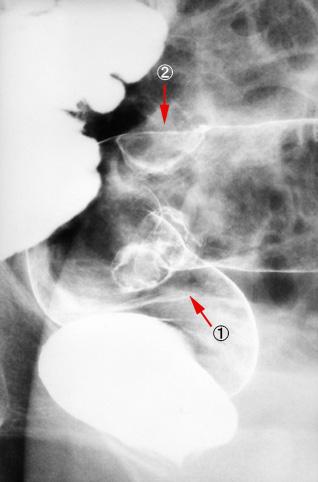

Criteria of Hist.ClassificationMalignant epithelial tumor/Adenocarcinoma

LocationLarge intestine(Colon)/Rectum

Technique, MethodX-ray

Macroscopic TypesType 2 Ulcerated type with clear margin/

Size25 - 29

Depth of Tumor Invasionmuscularis propria